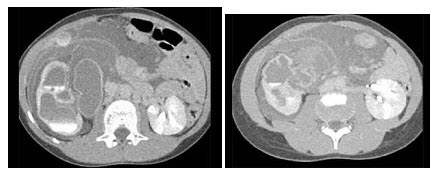

89、单项选择题

男,34岁,大腿下段疼痛2年,可摸到肿块,结合图像,最可能的诊断是()

A.骨肉瘤

B.软骨肉瘤

C.软骨瘤

D.纤维肉瘤

E.巨细胞瘤

90、单项选择题 正常头颅CT轴位鞍上池呈()

A.圆形或椭圆形

B.梯形或双梯形

C.三角形或梭形

D.长方形或方形

E.五角或六角形

91、单项选择题